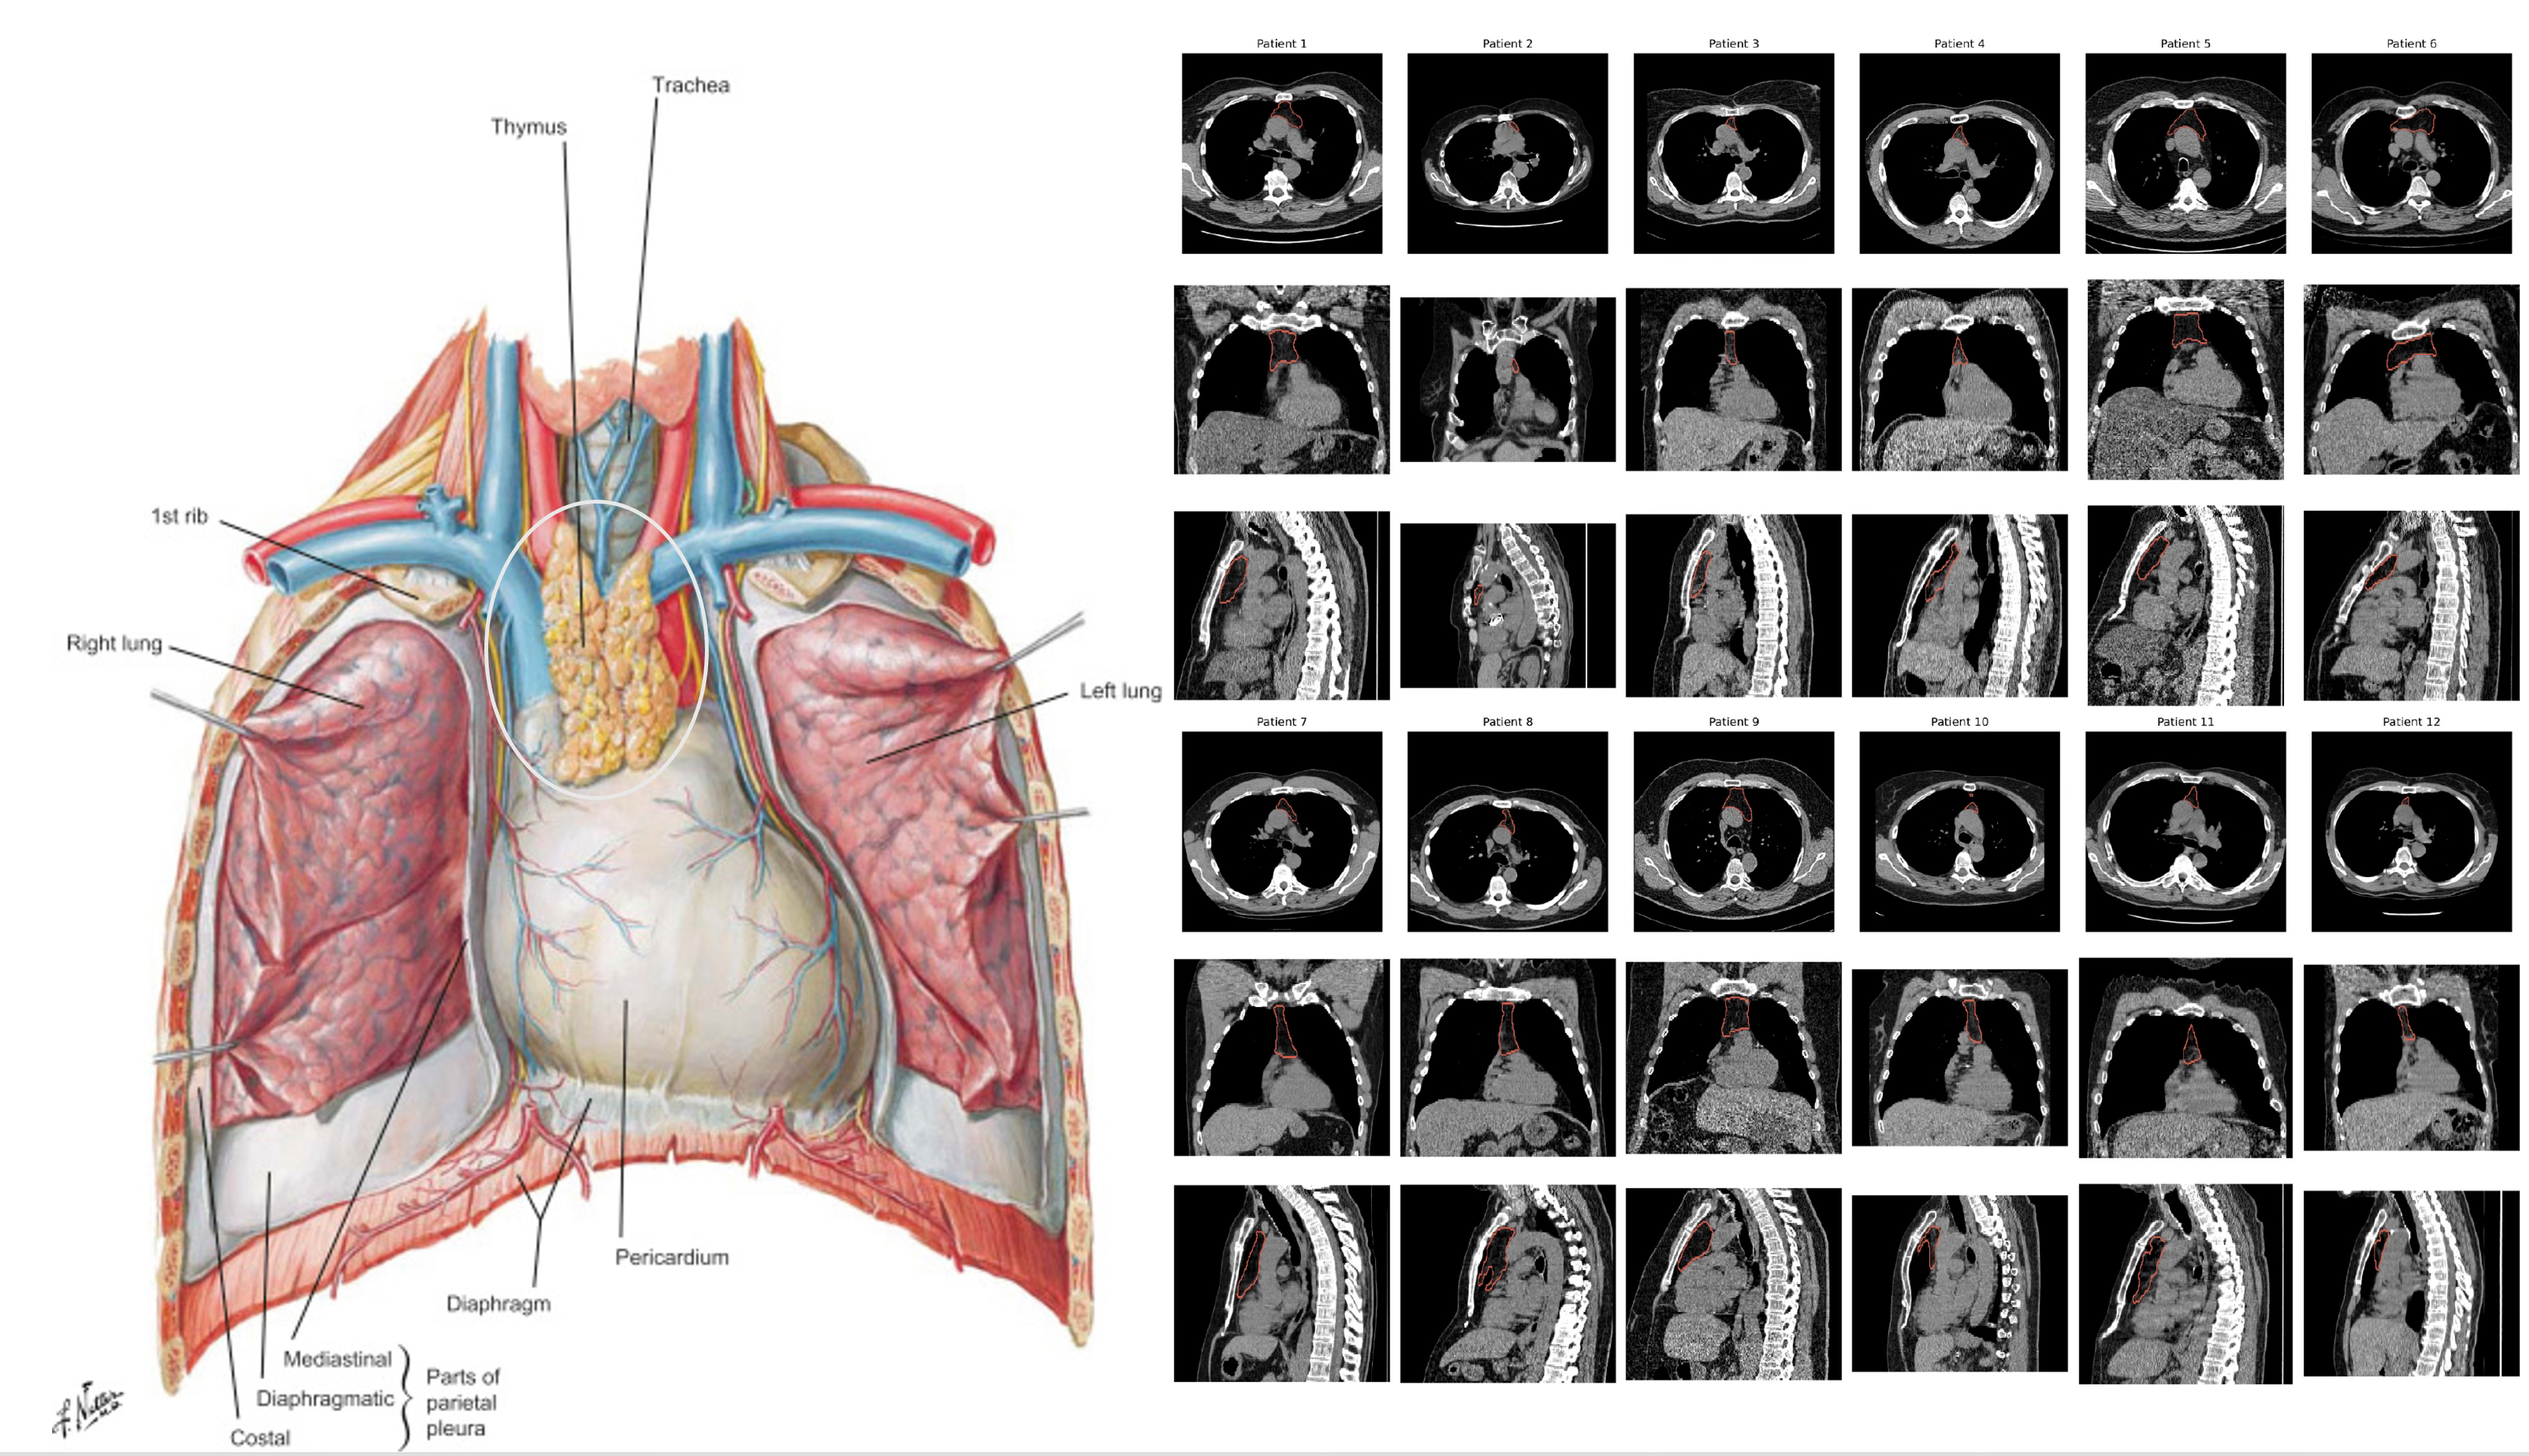

Our thymus gland plays a central role in the development of our immune system, specifically for supporting T cell development (how these cells got their name, maturation and differentiation in the thymus) and discriminating between self and foreign, non-self antigen proteins with production of dendritic cells. As we age, our thymus gland shrinks—the process known as involution—with progressive change from spongy to fatty tissue, with loss of functionality. But this process, with respect to timeline and extent, markedly varies from one person to the next. And to make things even more complicated, our thymus gland anatomy and precise location in the chest also is highly variable. So the famous Frank Netter diagrams from the 1960s (such as at left below) don’t capture the remarkable heterogeneity that a random set of 12 chest CT scans (below at right).